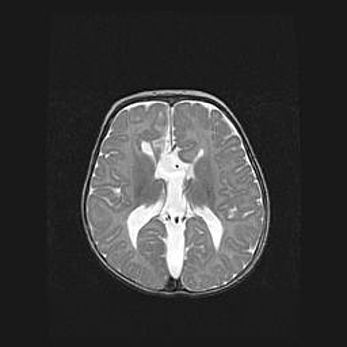

Аномалия Денди-Уокера. Признаки гипоплазии мозолистого тела.

Возраст: 5 месяцев 3 дня

Вес: 5550 г

Пол: мужской

Окружность головы: 39 см

Срок гестации: 40 недель

Аномалия Денди-Уокера – это порок развития головного мозга, для которого характерна триада симптомов: гипотрофия или аплазия червя мозжечка и/или полушарий мозжечка, расширение четвёртого желудочка с формированием ликворной кисты задней черепной ямки, гипертензионная гидроцефалия различной степени.

Гипоплазия мозолистого тела относится к дефектам внутриутробного этапа развития мозговой ткани, возникающим в процессе закладки структур головного мозга, что происходит на начальных этапах развития эмбриона.